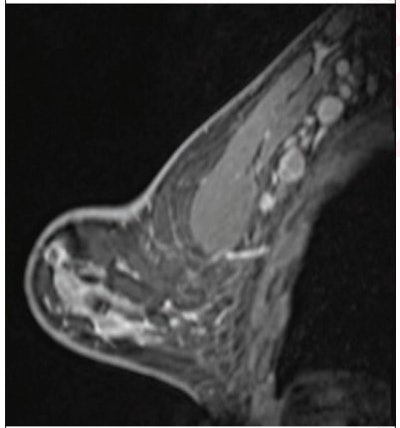

(Above) 55-year-old woman who underwent screening mammogram and ultrasound seven days after first COVID-19 vaccination dose. Screening mammogram and US demonstrated unilateral left axillary lymph node with cortical thickness of 5 mm on ultrasound (not shown). BI-RADS category 0 was assigned. Ultrasound from diagnostic work-up performed seven days later showed no change in lymph node size. BI-RADS 3 was assigned. (Below) 41-year-old woman who underwent high-risk screening breast MRI 15 days after first COVID-19 vaccination dose. Sagittal T1-weighted fat-saturated contrast-enhanced MRI shows extensive unilateral left level I-II axillary adenopathy. BI-RADS 3 was assigned. Images and captions courtesy of the American Roentgen Ray Society.

(Above) 55-year-old woman who underwent screening mammogram and ultrasound seven days after first COVID-19 vaccination dose. Screening mammogram and US demonstrated unilateral left axillary lymph node with cortical thickness of 5 mm on ultrasound (not shown). BI-RADS category 0 was assigned. Ultrasound from diagnostic work-up performed seven days later showed no change in lymph node size. BI-RADS 3 was assigned. (Below) 41-year-old woman who underwent high-risk screening breast MRI 15 days after first COVID-19 vaccination dose. Sagittal T1-weighted fat-saturated contrast-enhanced MRI shows extensive unilateral left level I-II axillary adenopathy. BI-RADS 3 was assigned. Images and captions courtesy of the American Roentgen Ray Society.